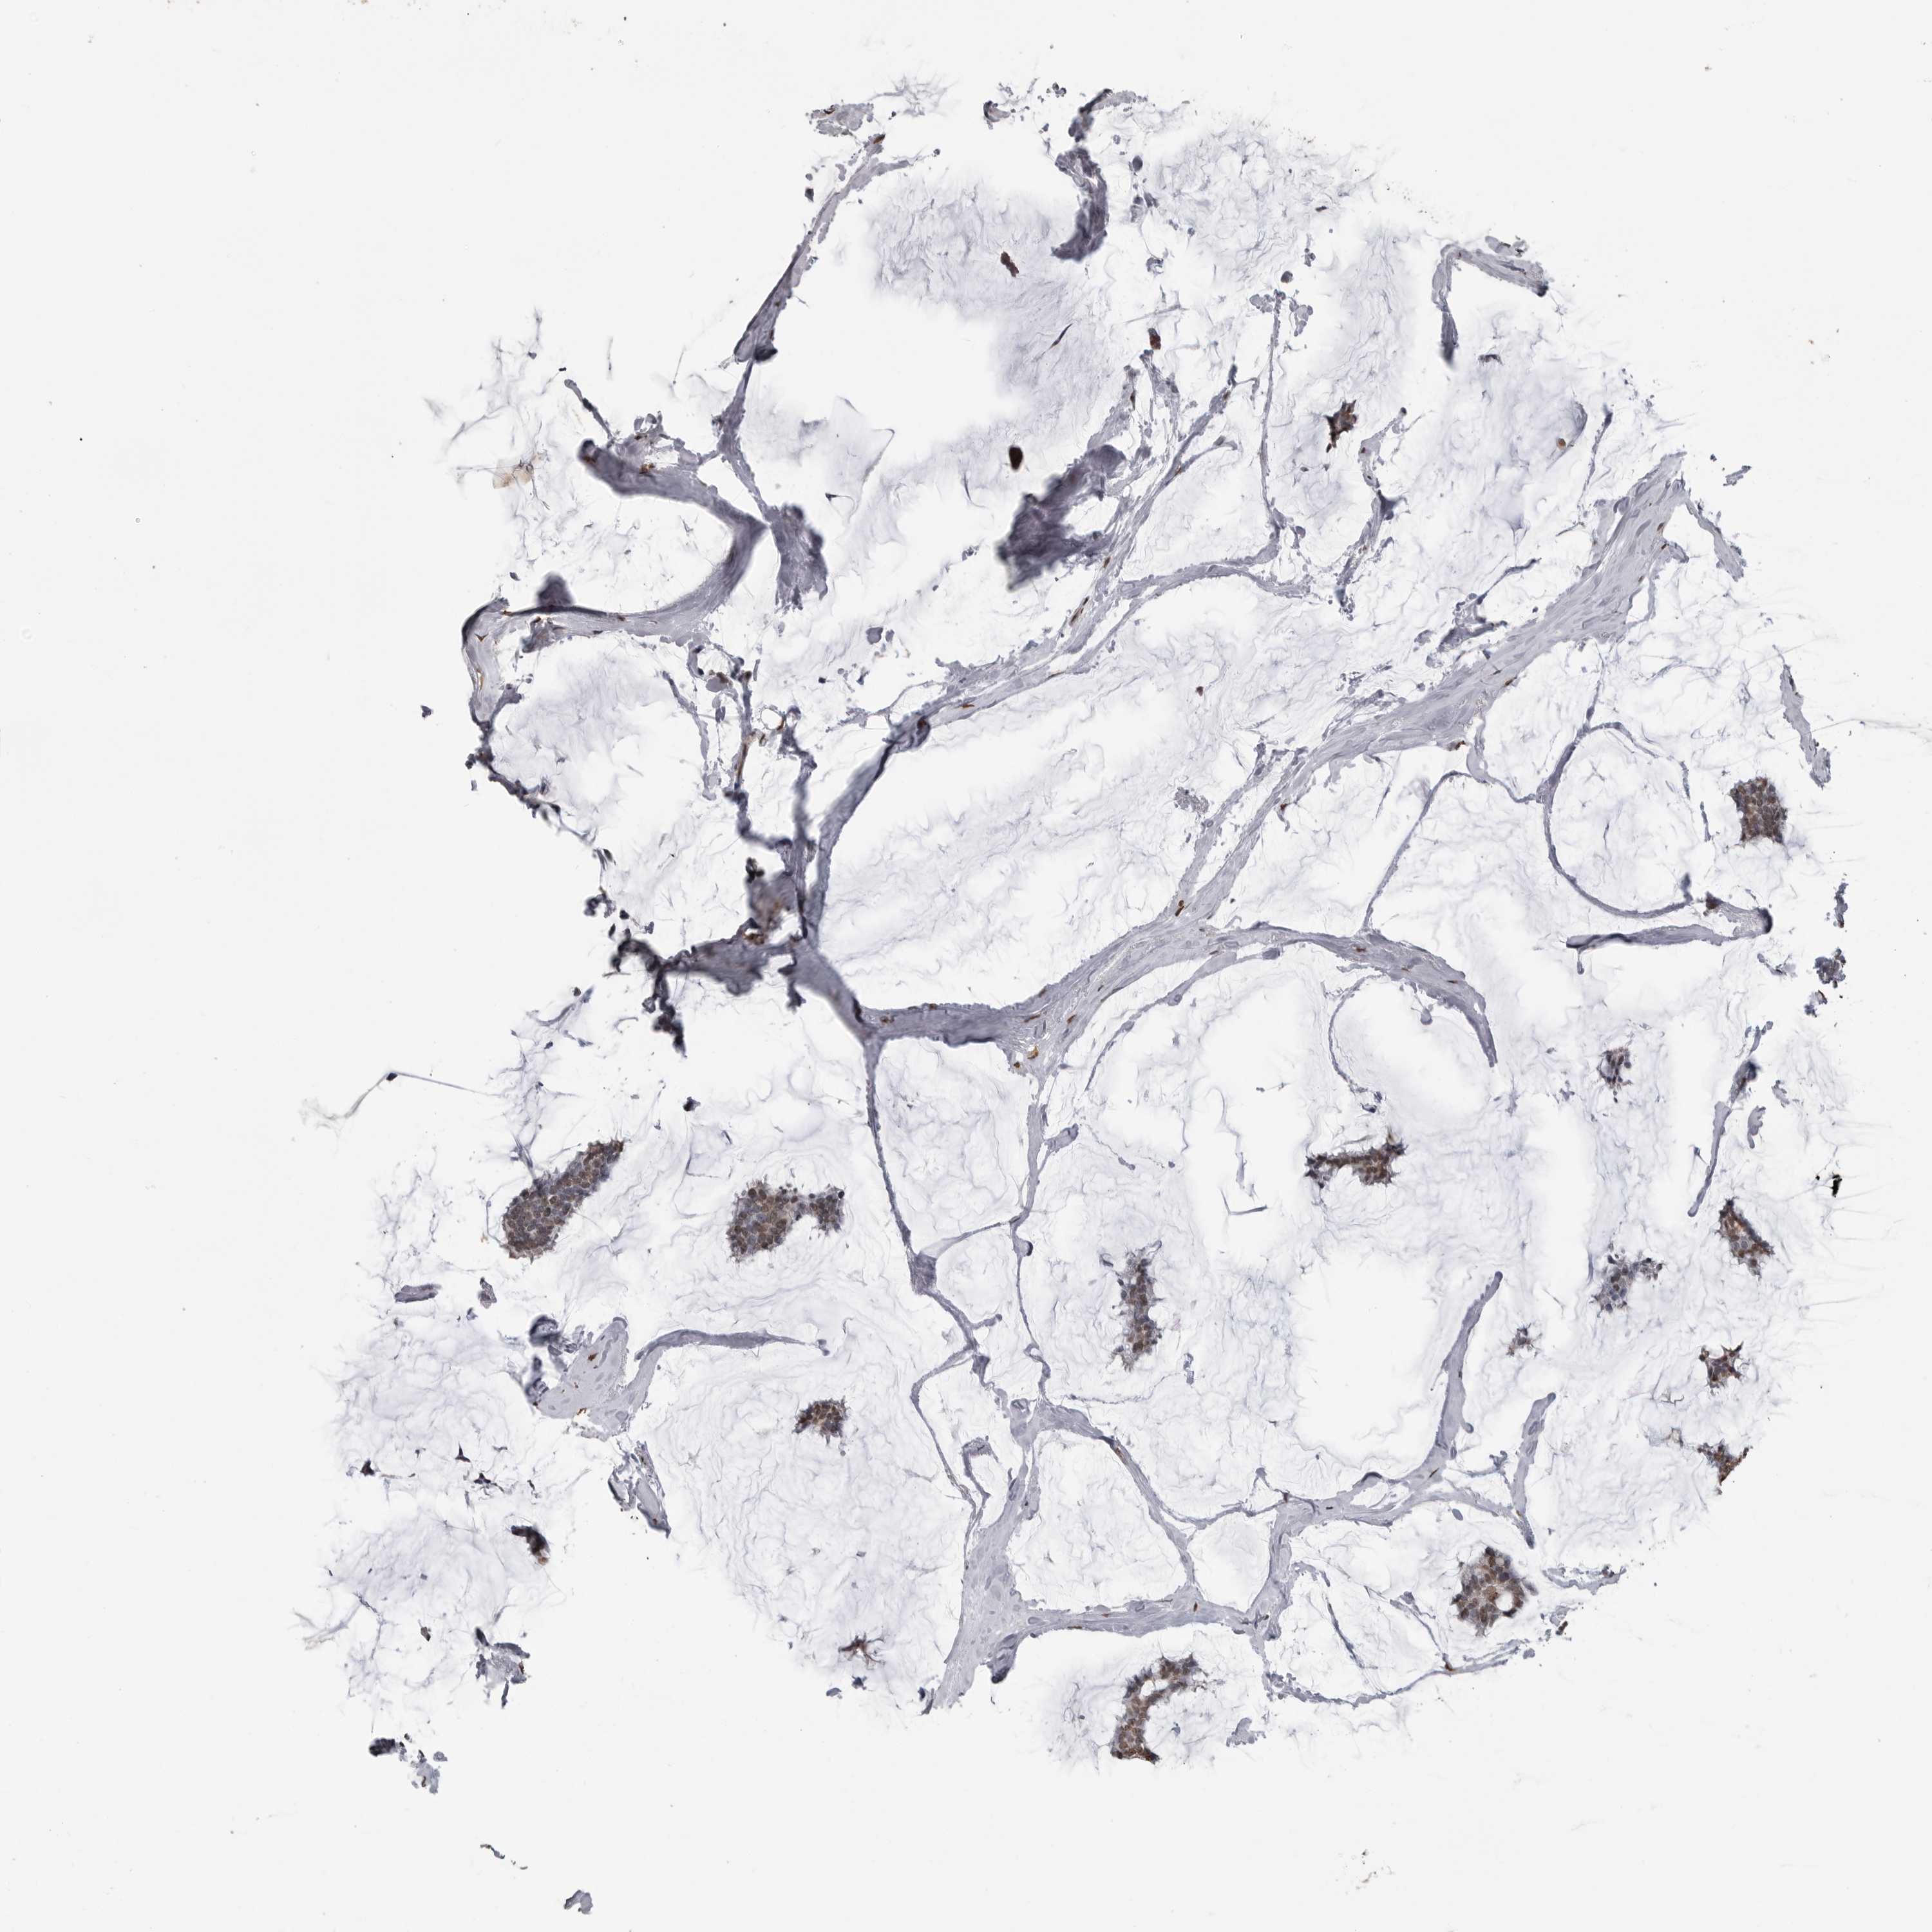

CANCER BREAST CANCER Show tissue menu

BRCA TCGA BRCA VALIDATION PROTEIN EXPRESSION

ANTIBODIES

AND

VALIDATION